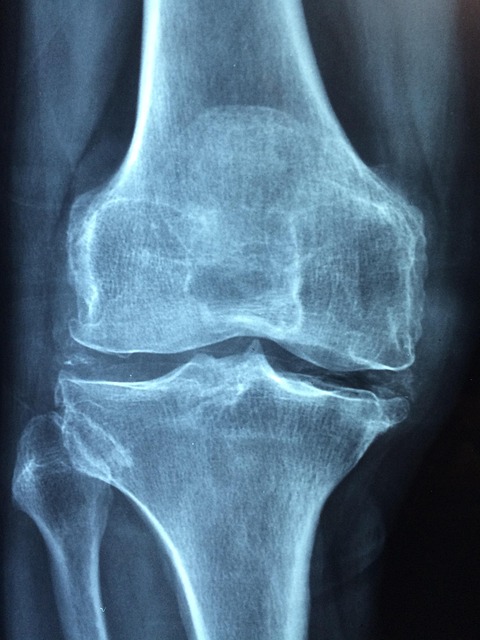

| 퇴행성 고관절염 | 전반적 | 아침 뻣뻣함, 보행 통증 |